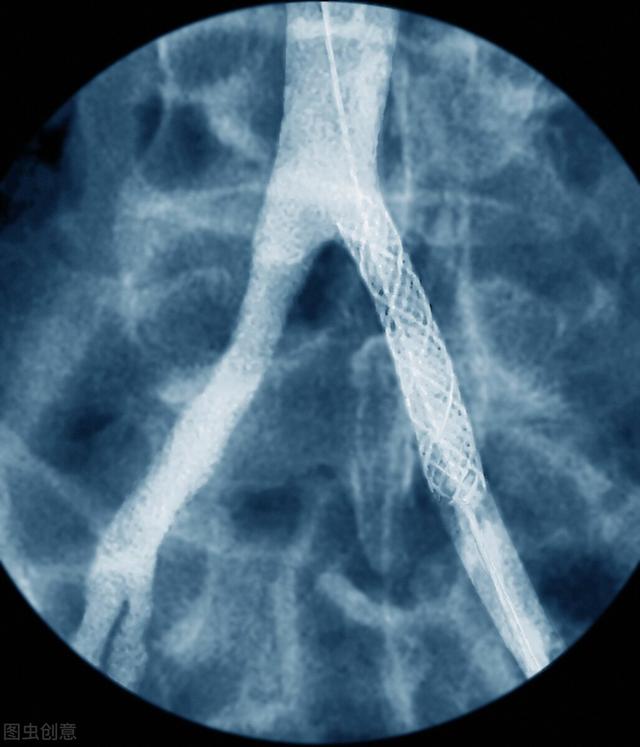

Par l'intermédiaire de l'artère radiale périphérique ou de l'artère fémorale et guidé par un fil-guide, un stent est placé dans la partie la plus étroite de l'artère coronaire, ce qui permet de dilater le vaisseau sanguin et de soulager l'ischémie, l'hypoxie et la nécrose.

L'endoprothèse cardiaque étant une opération réalisée dans une artère, un pansement compressif doit être appliqué sur le site de ponction après l'intervention afin d'éviter tout saignement postopératoire. En cas de ponction de l'artère radiale, il faut veiller à ne pas bouger la main de ponction pendant au moins 6 heures après l'opération pour éviter les saignements. En cas de ponction de l'artère fémorale, celle-ci étant une grosse artère avec une pression intravasculaire élevée, il est nécessaire de se reposer au lit pendant 12 à 24 heures après l'opération et d'éviter de sortir du lit pour faire de l'exercice.

Bien sûr, nous pouvons faire des activités appropriées après avoir enlevé le compresseur, mais dans le mois qui suit l'opération, il est toujours nécessaire d'éviter les activités physiques importantes et de se reposer pour faciliter le rétablissement. Si le degré de sténose de l'artère coronaire est inférieur à 50 % pendant l'opération, on parle d'athérosclérose coronaire ; s'il est supérieur à 50 %, on diagnostique une maladie coronarienne ; et si le degré de sténose est supérieur à 75 %, il s'agit d'une des indications pour la mise en place de stents cardiaques.

Les indications pour l'implantation d'un stent sont une sténose de l'artère coronaire supérieure à 75 %, des crises d'angine de poitrine fréquentes ou un infarctus aigu du myocarde. Une fois le stent implanté, il est nécessaire d'insister sur l'amélioration du mode de vie et la prise régulière de médicaments, et de prêter attention à la surveillance des changements de l'état et à l'examen régulier, et si nécessaire, de réimplanter le stent ou de subir un pontage aorto-coronarien pour stabiliser l'état, le contrôler et réduire les complications. Si nécessaire, il convient de réimplanter un stent ou de procéder à un pontage coronarien afin de stabiliser et de contrôler la maladie et de réduire les complications.